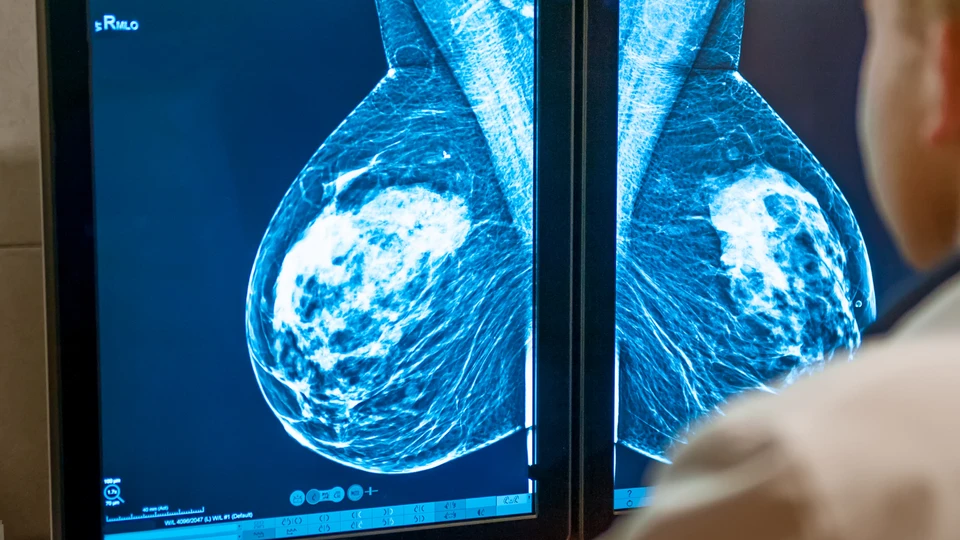

Forsinket diagnose af brystkræft - tildelt erstatning

En 55-årig kvinde fik en mammografi i 2017, fordi hun havde opdaget en hævelse i sin armhule. Undersøgelsen viste, at alt så normalt ud. I 2019 fik kvinden en mammografiscreening som del af screeningsprogrammet. Her viste det sig, at kvinden havde brystkræft, og hun måtte gennemgå to operationer og efterfølgende kemoterapi.

Patienterstatningens vurdering

Patienterstatningen vurderede, at man allerede på billedmaterialet fra 2017 kunne se forandring i det ene bryst. Kvinden fik erstatning, fordi man burde have opdaget denne forandring, taget en biopsi og opdaget brystkræften.

Erstatning

Den forsinkede diagnose gjorde, at kræften spredte sig og blev uhelbredelig. Kvinden fik 470.000 kr. i erstatning. Erstatningen blev givet som godtgørelse for et varigt mén på 50 % og en forlænget sygeperiode.

Méngraden blev fastsat til 50 %, da kvinden trods den uhelbredelige brystkræft var fysisk velbefindende. Ved sagens afslutning informerede Patienterstatningen kvinden om, at sagen kunne genoptages, hvis hendes tilstand blev forværret. I så fald ville det varige mén kunne forhøjes til 100 %, og kvinden ville have ret til yderligere erstatning.